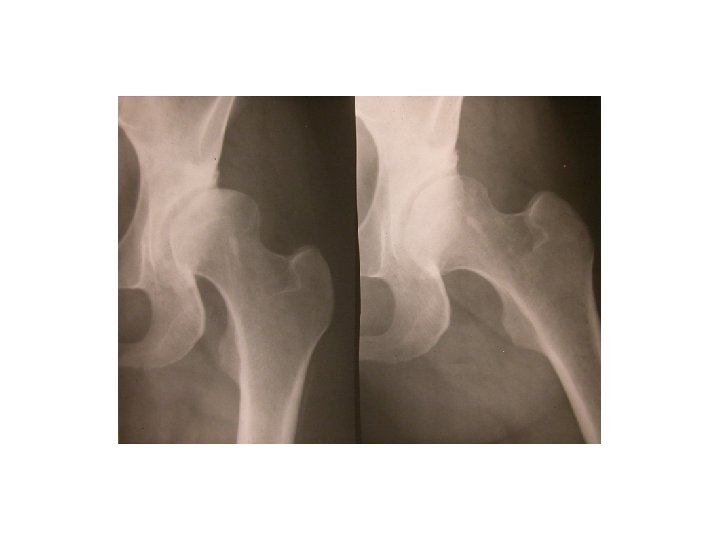

SEMIOLOGIE DE LA HANCHE J-P ESCHARD • Anatomie Articulation profonde Articulation très emboîtée mobilité

SEMIOLOGIE DE LA HANCHE J-P ESCHARD • Anatomie Articulation profonde Articulation très emboîtée mobilité réduite

SEMIOLOGIE DE LA HANCHE 3°Signes d’examen (signes physiques): Etude des mouvements Mouvements passifs+++: le

SEMIOLOGIE DE LA HANCHE 3°Signes d’examen (signes physiques): Etude des mouvements Mouvements passifs+++: le coxogramme Mouvements combinés Mouvements actifs

SEMIOLOGIE DE LA HANCHE 3°Signes d’examen (signes physiques): Etude des mouvements Mouvements passifs+++: le coxogramme flexion/extension/abduction/adduction RE/RI Mouvements combinés Mouvements actifs : étude des muscles et des tendons: le moyen fessier++ 4° Examen régional: neurologique amyotrophie